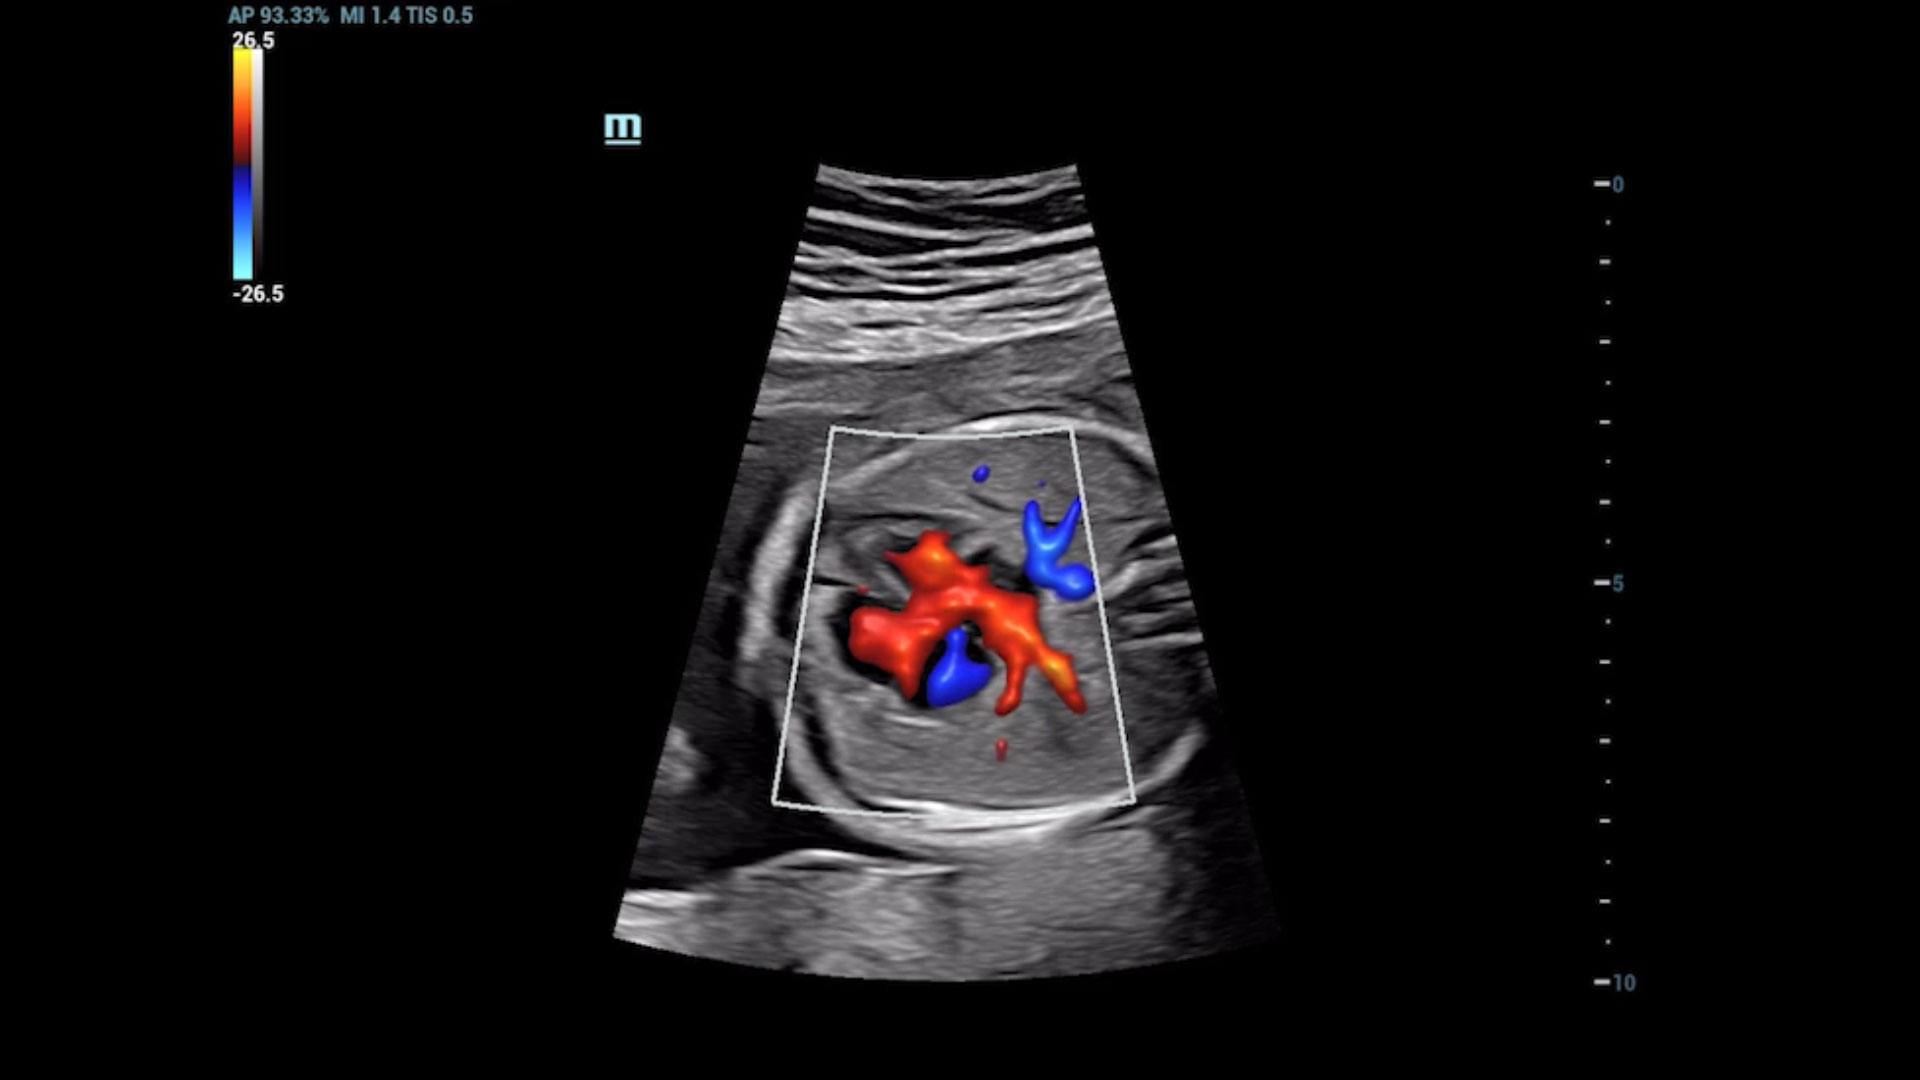

UMA (angiografia ultramicroscĆ³pica)

A tecnologia inovadora elimina as limita??es das tradicionais imagens com Doppler. Com resolu??o espacial e sensibilidade de fluxo ultra-altas, permite a detec??o de perfus?es de fluxos muito sutis e lentos, ampliando assim a aplica??o clĆnica da avalia??o qualitativa e quantitativa do ultrassom no cĆ©rebro fetal, rins, placentas, endomĆ©trios, ovĆ”rios etc.

UMA ā Fluxo uterino e endometrial